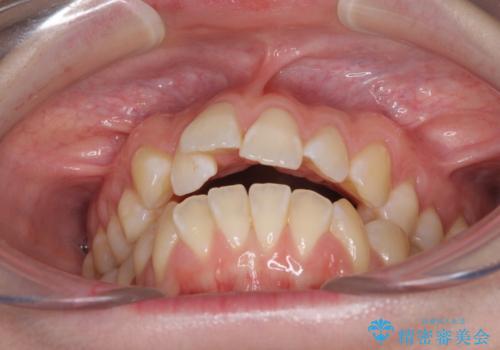

気になるデコボコとオープンバイト インビザラインでの矯正治療

- 前歯のデコボコと上下が開いていることを気にして来院された患者様です。

いわゆるオープンバイトは、インビザラインによる治療が適しているため、インビザラインにて治療を行うこととしました。

オープンバイトは容易に後戻りを起こすため、少しでも後戻りリスクを軽減するために舌癖改善のトレーニングをしっかりと行っていただきました。